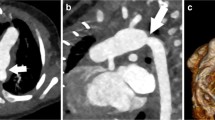

There were three patients who had a biphasic CTA performed due to the diagnosis of thromboembolic disease on a prior monophasic CTA, one of which had been performed at an outside institution. Two of these three patients’ diagnoses were reversed based on follow-up biphasic CTAs. One of the two patients whose diagnosis was reversed presented to clinic with a 9-day history of chest pain and shortness of breath brought on by stress at work. An outpatient, monophasic CTA was obtained that was concerning for a Fontan thrombus due to suboptimal opacification of the central left pulmonary artery while there was good opacification of the distal left pulmonary artery (Fig. 1a, b). The other patient whose diagnosis was reversed had a history of chronic mycobacterium avium-intracellulare with associated chronic hemoptysis. This patient presented to an outside hospital with a more severe episode of hemoptysis. As part of the evaluation, a monophasic CTA was obtained that was reported to be concerning for “complete occlusion of the stent extending from the inferior vena cava to the pulmonary artery outflow tract.” The third patient was admitted to the hospital with plastic bronchitis awaiting heart transplantation while on room air. They developed poor perfusion with associated emesis and acute worsening of their ventricular function on echocardiogram that ultimately led to respiratory failure requiring intubation. On chest X-ray, there were findings consistent with pneumonia in the right lower lobe. However, there were persistent abnormalities on follow-up chest X-rays that could be attributed to a thromboembolic etiology as opposed to a right lower lobe pneumonia. Therefore, a monophasic CTA was obtained to evaluate for thromboembolic disease. On this CTA, there was concern for Fontan thrombus due to a filling defect in the distal right pulmonary artery and the branches to the right lower lobe. In addition to the filling defect, there was evidence of pulmonary infarction due to a triangular parenchymal opacity that abutted the pleural margin with internal air bronchograms peripheral to the branches of this right lower lobe pulmonary artery. This clinical presentation was felt to be consistent with Fontan thromboembolic disease and the patient was treated with anticoagulation. This patient’s follow-up biphasic CTA was performed one week after the initial monophasic CTA and its negative finding was attributed to anticoagulation treatment. There was one patient with Fontan circuit thrombus noted on a monophasic CTA, whose diagnosis was reversed based on follow-up cardiac MRI. This patient presented to the emergency department, while pregnant at 32 weeks of gestational age, with sharp sternal chest pain. The monophasic CTA that was obtained was unable to rule out thromboembolic disease due to streaming of contrast. Therefore, of the 5 positive monophasic CTAs, two were subsequently found to be falsely positive (Table 3).

One patient was diagnosed with a Fontan thrombus by a biphasic CTA due to a contrast filling defect in the left lower lobar pulmonary artery. In addition to the contrast filling defect noted on the CTA, the presence of heterogeneous lung attenuation and ground glass opacity in the left lower lobe also supported the diagnosis of a pulmonary embolism. The CTA was obtained due to clinical symptoms of acute onset of chest tightness and shortness of breath. As such, there were no patients diagnosed with Fontan thrombus on a biphasic CTA, whose diagnosis was later reversed.